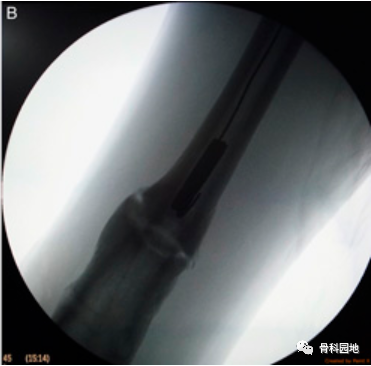

钓鱼技术用于取回髓内钉远端断裂部分。取了一根 20 号长的不锈钢线,其长度足以到达并取回断裂的钉子。如上所述,在其一端制作了一个钉钩。将去除的钉子近端部分用作模板,以按照所需的尺寸制作钩子。在透视引导下,钩子沿着髓管向下传递,然后穿过断裂的钉子,使得整个钩子位于钉子远端()。

然后将不锈钢丝拉近端以钩住断裂的钉子。然后通过轻轻地将不锈钢线拉出来取回钉子(图B)。